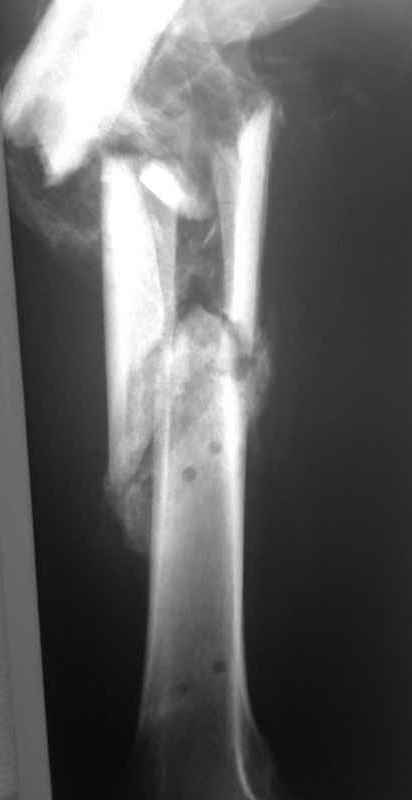

Re: Неправильно срастающийся оскольчатый перелом бедра

Спасибо за снимки. Предложения по тактике прежние.